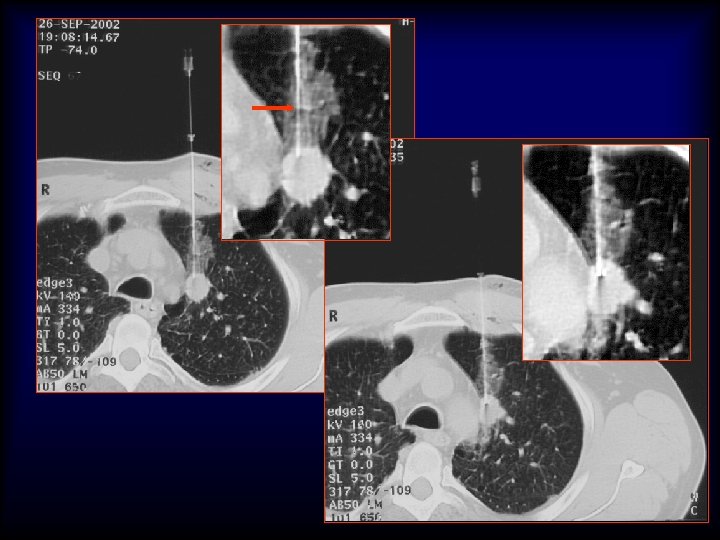

20 G/9 cm/10 T x 25 x 40 x 200 5 mm Adenocarcinoma H&E